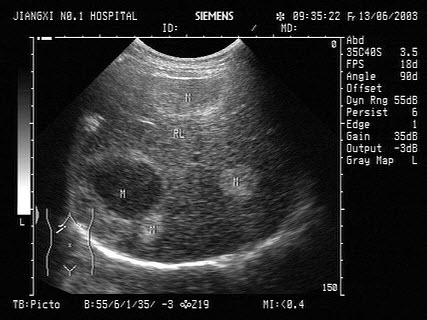

10、单项选择题

男、30岁,体检时发现脾门处光团,根据超声声像图诊断为()